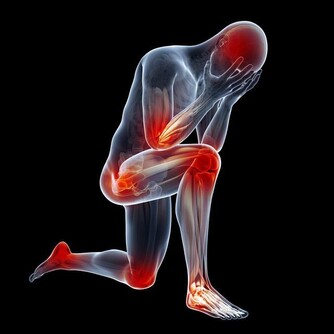

若有自體免疫疾病,如類風濕性關節炎、系統性紅斑狼瘡等,則須配合同時治療;